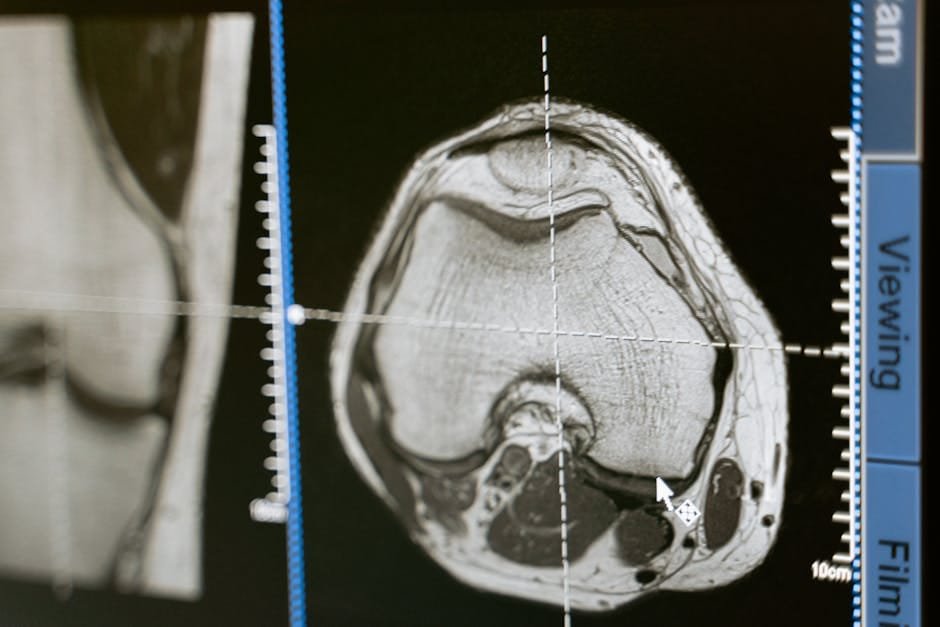

PET/CT lesion profiles matched tuberculosis treatment outcomes in marmosets

Imaging shows why some TB drug combinations work better than others